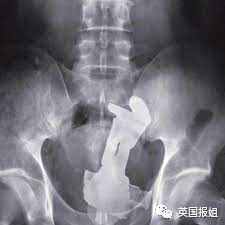

一名军迷男子下体塞入了一枚17cmX6cm的二战时期反坦克炮弹,当然,他说是滑倒造成的。

医生非常慌,就算她医术再高明,也是没有进行过军械拆卸的,于是她职业生涯中第一次报警叫来了拆弹部队。

经过了拆弹部队和医院多个诊室的会诊,终于判定炮弹已没有引爆危险,在复杂的手术后将其取出。